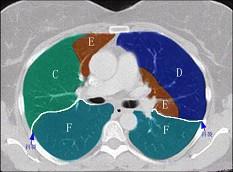

问题 结合肺段模式肺动脉干与右肺动脉层面肺动脉干与右肺动脉层面(见图), 心室层面(见图), 主动脉弓层面(见图), 左右心房层面(见图),选出左肺上叶的组成 ( )

选项 A、A+B+C+D+E B、A+B+C+D+E+F C、A+B+C D、A+B+C+D E、A+B

答案 A